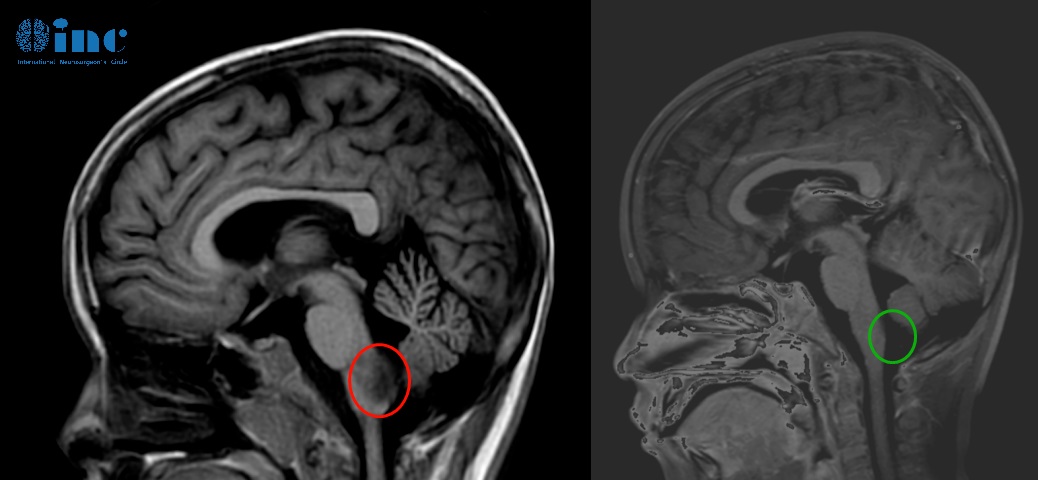

1、6岁男孩——脑干-延髓毛细胞星形细胞瘤

病情分析:偶然发现脑干占位性病变,一开始国内手术,考虑到手术风险,只切除了较小部分的肿瘤组织。复查核磁提示肿瘤进展,医生建议化疗。

治疗难点:所处位置在人体的“生命中枢”脑干-延髓之上,延髓控制着人体的吞咽、呼吸登基本功能,一旦等待肿瘤长大,占位效应会更加明显。手术的风险也较大,想要尽可能切除肿瘤又不伤及正常的脑组织,对于主刀医生的技术要求高。

手术结果:巴教授顺利近全切肿瘤,术后三天查房交流清晰、肢体抓握能力正常、术后食欲正常,术后两个多月,孩子正常回归学校。